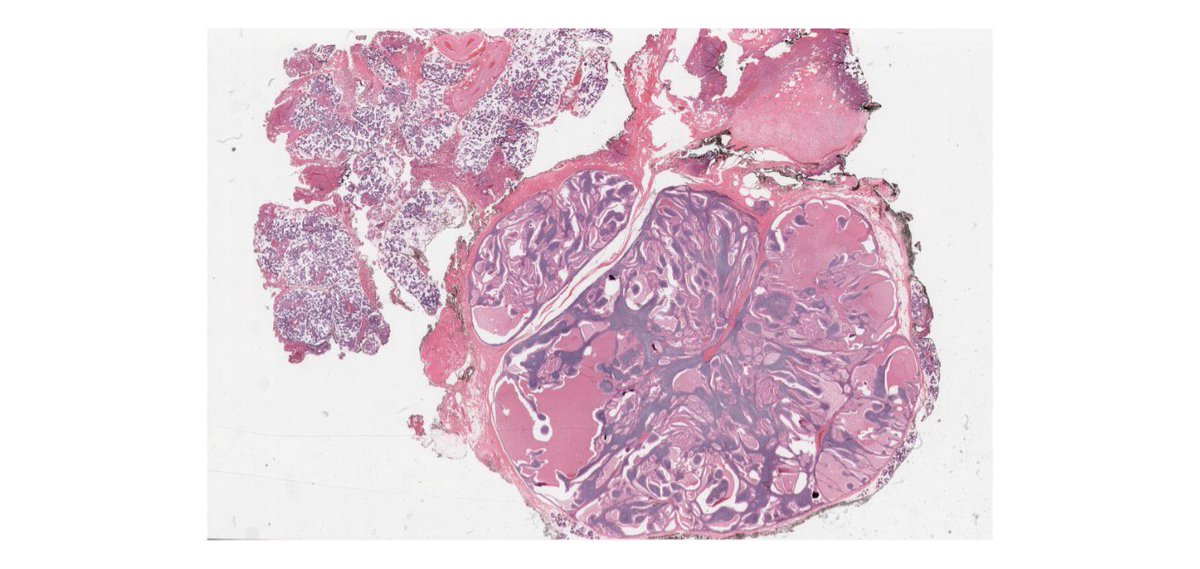

Case 8:

Benign salivary gland neoplasm composed of oncocytic epithelial cells lining papillary, ductal and cystic structures within rich lymphoid stroma

Note: the double layer of oncocytic epithelial cells